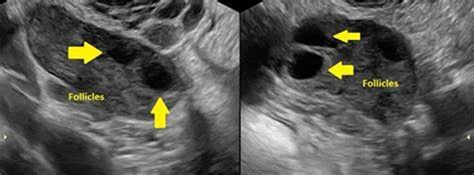

Polycystic Ovary Syndrome is a health condition characterized by enlarged ovaries containing small groups of fluid-filled sacs. This condition significantly impacts a woman’s hormonal balance. Typically, women between the ages of 15 and 44 may experience this health issue. A definitive diagnosis is crucial to receive appropriate treatment. Our gynaecologist emphasizes the importance of screening for early detection and prevention.